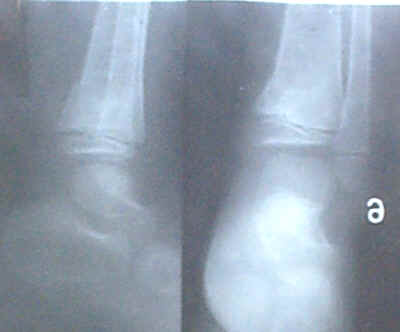

龙乃良,男,汉族,出生于1995年9月9日,住江西省万载县三兴乡红旗村6组。1999年3月15日在姑父家玩时被晒垫压伤右脚,当天在三兴卫生院摄片诊断为右脚股骨骨折,并严重错位。由其姑父医治七天,伤处皮肤发炎开烂,伤势恶化。其父担心致残赶紧把他接回家,第八天清晨请我去医治。我用手法先使折骨复位,用两张大号膏药贴在伤处没烂处,烂处涂上消炎药,第二次也用两张大号膏 ,第三次用一张大号膏药。该小孩20多天后能下地走动,一个月后和其他小朋友一样追跑。